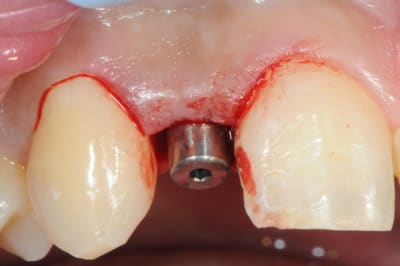

je reviens sur ce cas que j'ai un peu délaissé...

-cicatrisation

-mise en place vis de cica petit diamètre

-ensuite on augmente le diamètre en conservant et en gonflant les tissus gingivaux